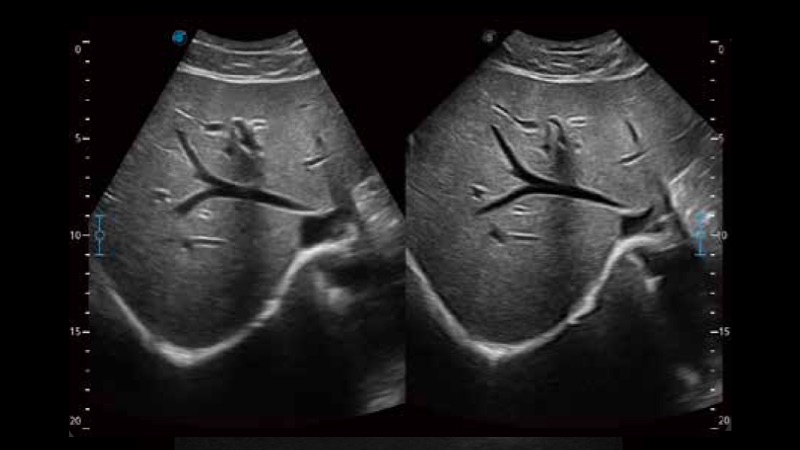

单晶体凸阵探头

凭借狗万官方网站先进的成像技术和优异的探头技术提供的清晰的图像表现,您可以更自信地做出临床决策。